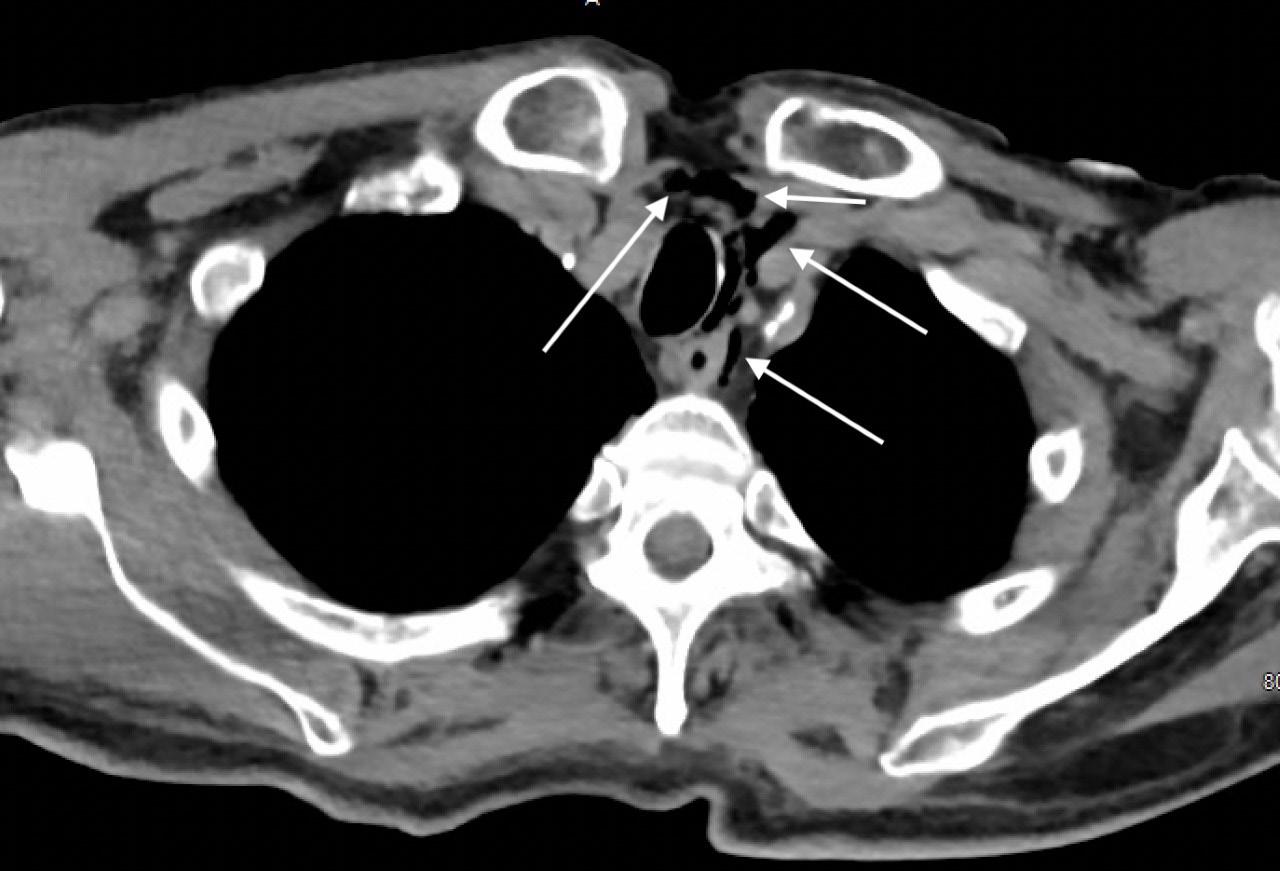

Image 2. Portable chest radiograph of a 44-year-old man with hemoptysis and hypoxemic respiratory failure showing diffuse bilateral coalescent airspace opacities with air bronchograms (black arrows). Table 2. Laboratory studies to consider in the work-up of massive hemoptysis.

This leads me to the patient’s imaging, which is often key to reaching a final diagnosis in patients presenting with hemoptysis. As noted earlier, advanced imaging such as computed tomography (CT) is only possible once the patient has been sufficiently stabilized. Therefore, many physicians may have to initially rely on a portable chest radiograph (CXR) alone. A CXR is a bit of a mixed bag, with widely variable rates of diagnostic ability reported in the literature. Sometimes it can identify a localizing lung lesion such as a tumor or cavitation, or potentially a more diffuse process such as pneumonia or diffuse alveolar hemorrhage. This patient’s CXR fits more in the latter category with diffuse bilateral airspace disease and air bronchograms. It is fortunate that he was also able to receive a CT angiography (CTA), as this is often the ideal imaging study to identify the cause of bleeding in hemoptysis, especially if it is from a culprit lesion. As most cases of massive hemoptysis are from the bronchial arterial system, it is worth noting that this CTA should ideally be protocoled differently from the traditional pulmonary artery CTA used when evaluating for pulmonary embolism.1 This patient’s post-intubation CTA demonstrated widespread ground-glass opacities with prominent septal lines, dependent consolidation, and air bronchograms in the bilateral lung bases suggestive of diffuse alveolar hemorrhage and hemorrhagic pneumonia.